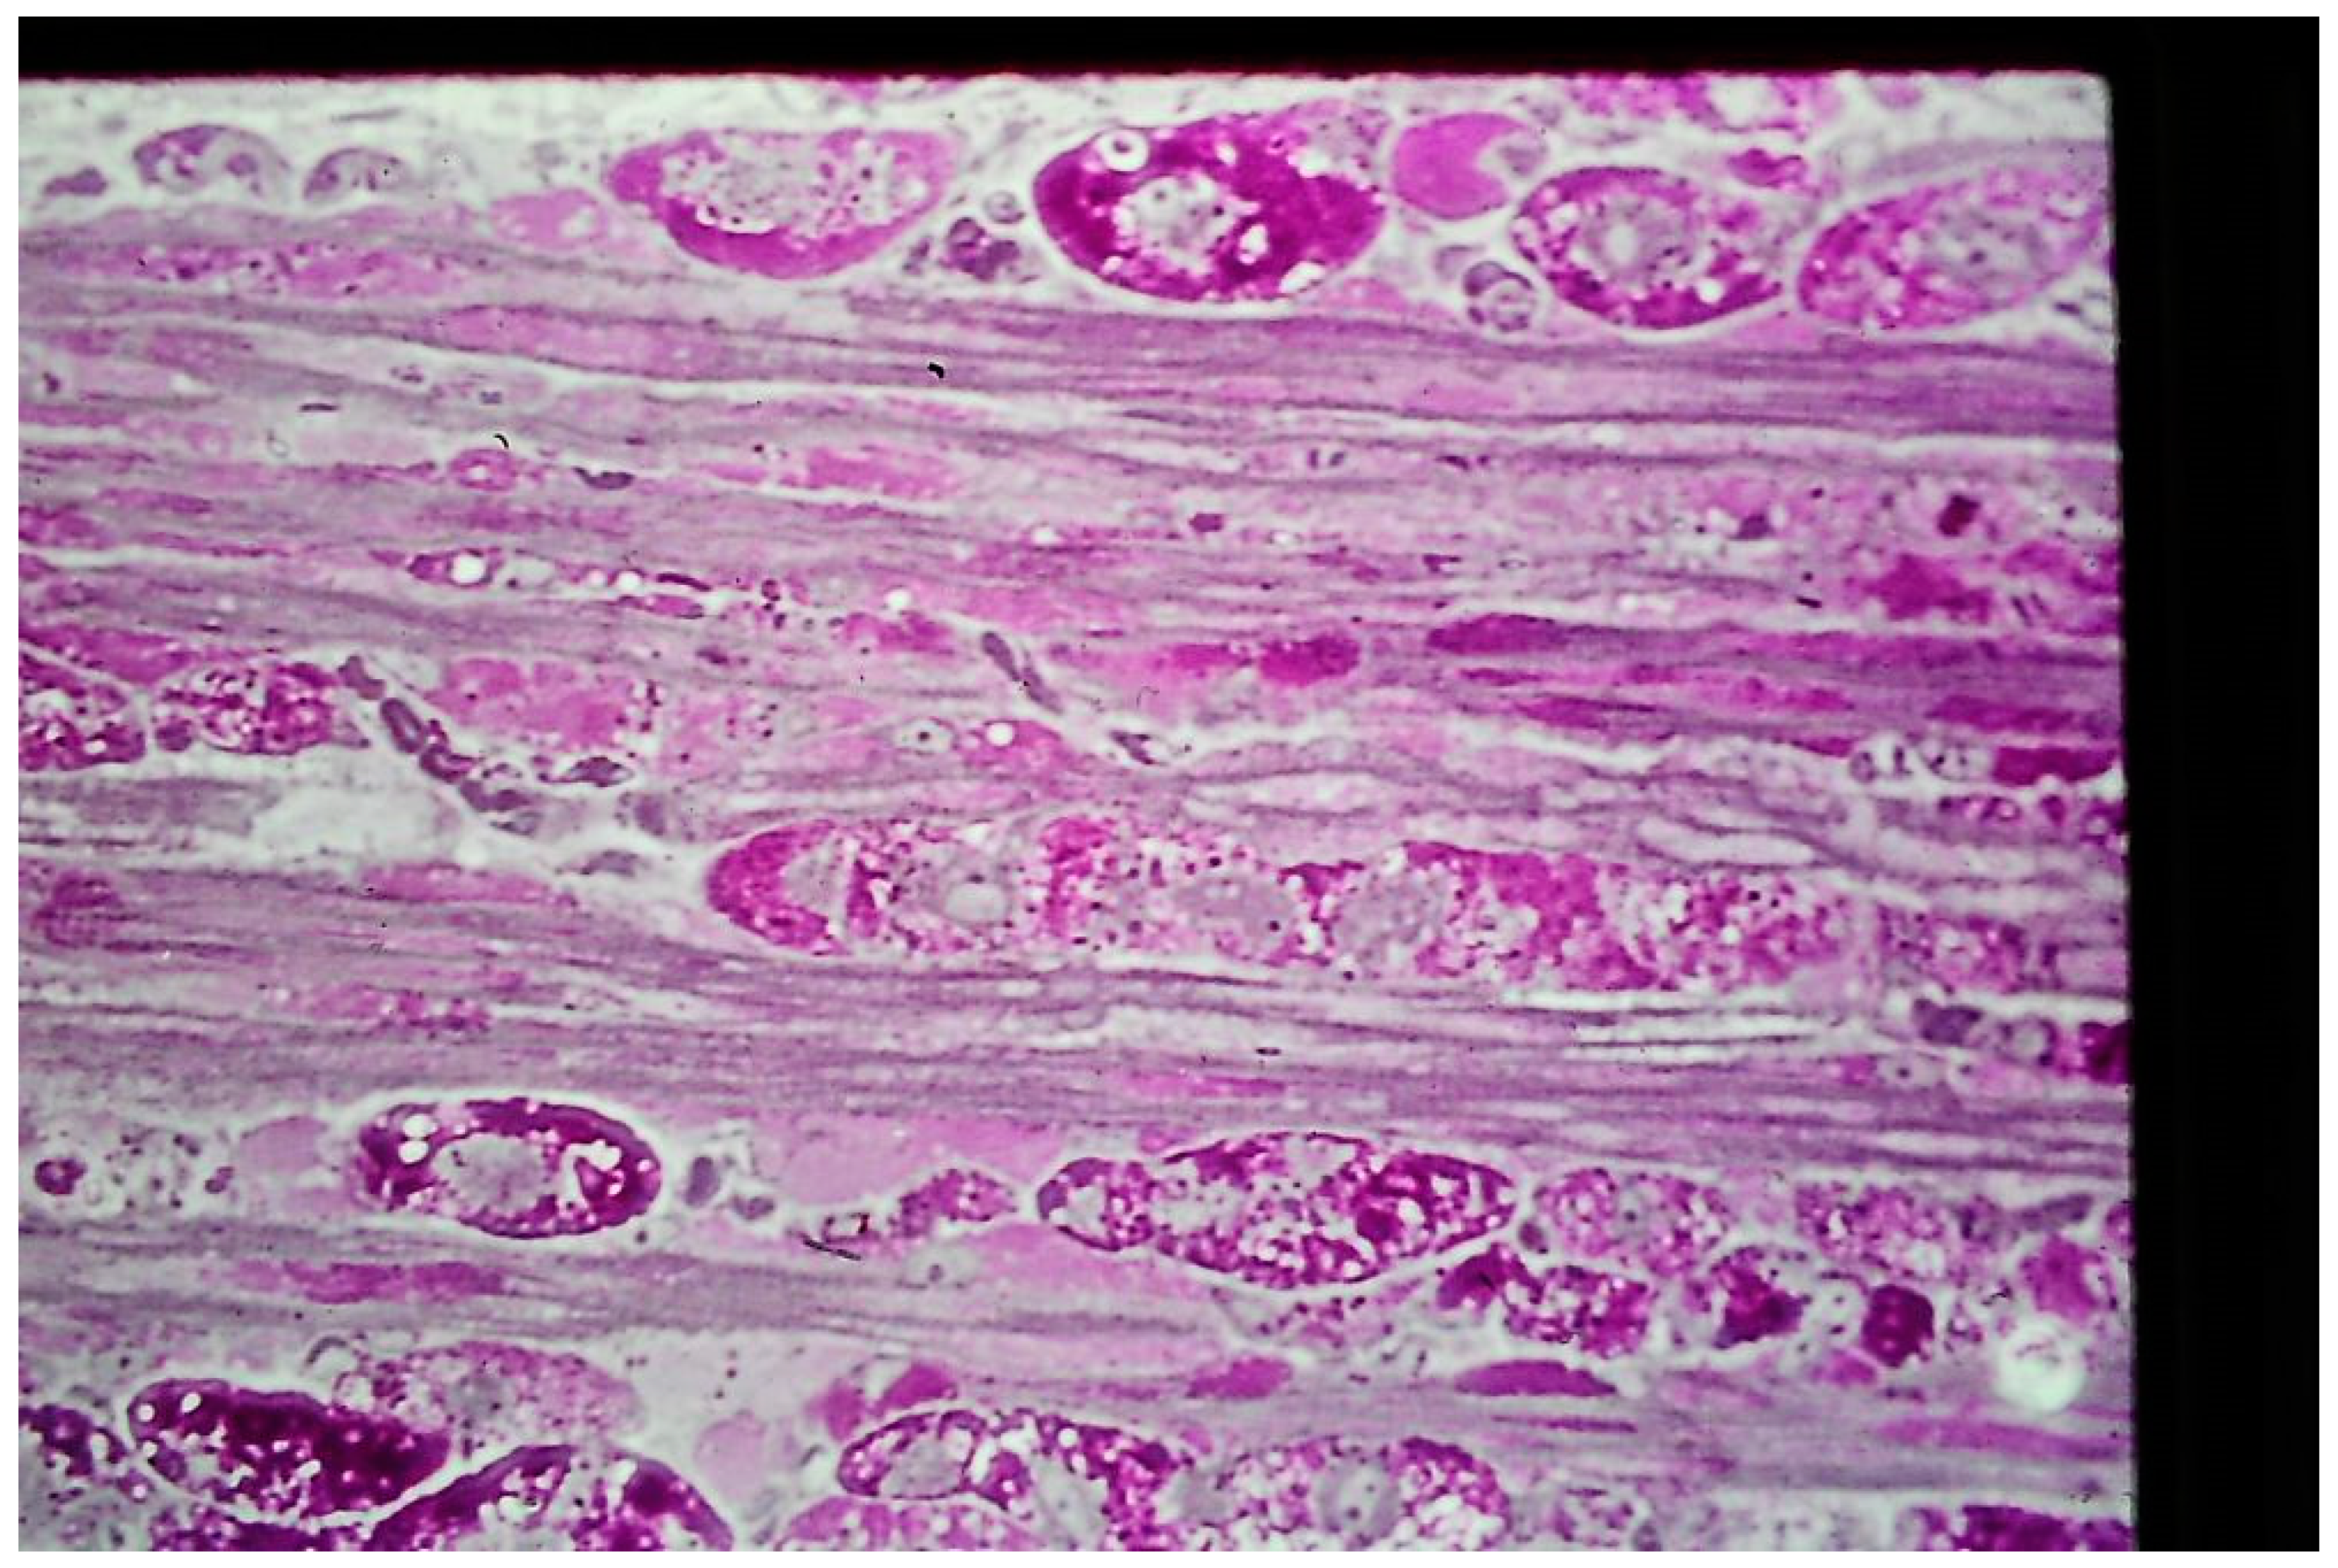

3.2. Acid Maltase Deficiency

18. Mitochondrial Myopathy

19. Megaconial Mitochondrial Myopathy

20. Multiple acyl-CoA Dehydrogenation and CoQ10 Deficiency

29. Mitochondrial Neurogastrointestinal Encephalomyopathy (MNGIE)

30. Myoclonus Epilepsy with Ragged Red Fibers (MERRF)